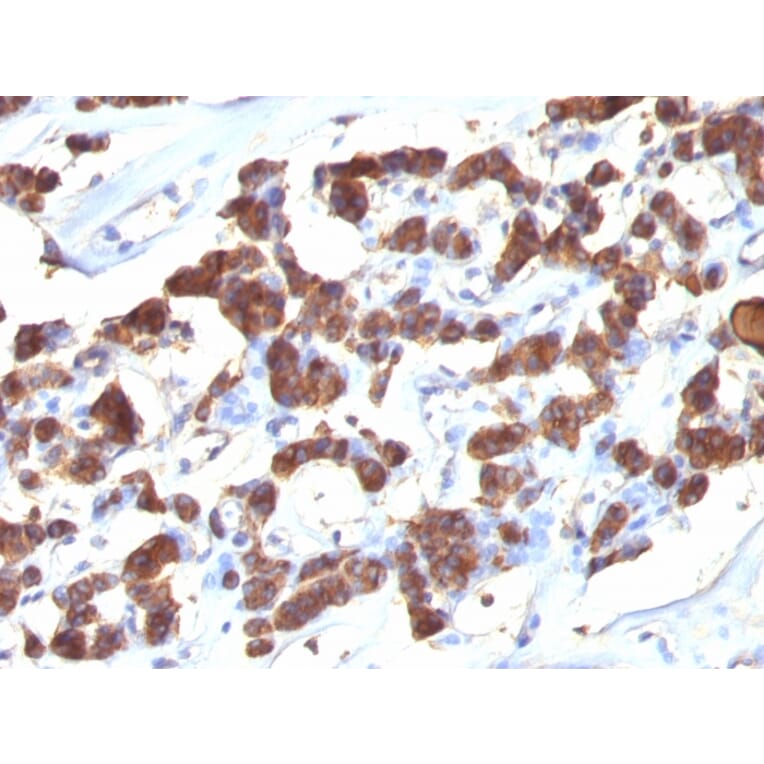

Anti-Thyroglobulin Antibody [2H11 + 6E1] (A250107)

Mouse monoclonal [2H11 + 6E1] antibody to Thyroglobulin for Flow Cytometry and IHC-P.

Thyroglobulin is a 660kDa dimeric pre-protein with mutiple glycosylation sites. It is produced by and processed within the thyroid gland to produce the hormone thyroxine and triiodothyronine. Prior to forming dimers, thyroglobulin monomers undergo conformational maturation in the endoplasmic reticulation. The vast majority of follicular carcinomas of the thyroid will give positive immunoreactivity for anti-thyroglobulin even though sometimes only focally. Poorly differentiated carcinomas of the thyroid are frequently anti-thyroglobulin negative. Adenocarcinomas of other-than-thyroid origin do not react with this antibody. This antibody is useful in identification of thyroid carcinoma of the papillary and follicular types. Presence of thyroglobulin in metastatic lesions establishes the thyroid origin of tumor. Anti-thyroglobulin, combined with anti-calcitonin, can identify medullary carcinomas of the thyroid. Furthermore, anti-thyroglobulin, combined with anti-TTF1, can be a reliable marker to differentiate between primary thyroid and lung neoplasms.

Flow Cytometry, IHC-P

Flow Cytometry: 0.5-1 µg/million cells, IHC-P: 1-2 µg/ml